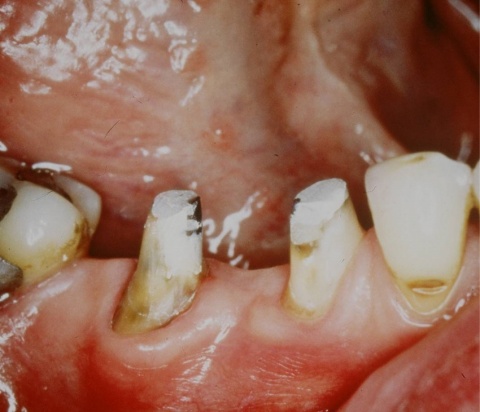

Eine Schnittstelle zu den bereits ausgeführten parodontalen Voraussetzungen des Zahnerhalts ergibt sich bei kombinierten Paro-Endo-Läsionen beziehungsweise Endo-Paro-Läsionen. Zeigen konservative Behandlungsansätze bei den meisten dieser Befunde gute Ergebnisse, ist bei einem lokal ausgeprägten Knochenabbau zumeist die chirurgische Intervention zum Zahnerhalt notwendig (Abb. 11 und 12). Wichtig dabei ist die Unterscheidung der primären Ursache (primär endodontische oder primär parodontale Ätiologie) der Läsion und einem dieser Ursache angepasstem Behandlungsprotokoll.